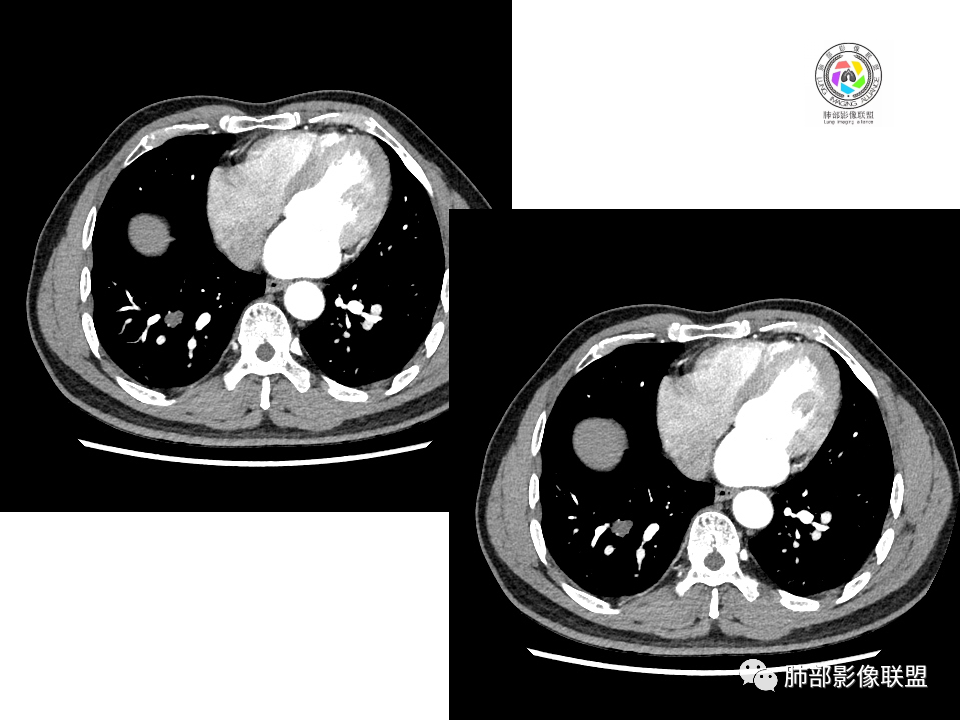

血管也是稍推移,在边缘,病灶密度均匀,边缘稍收缩;均匀强化;

这两个病灶的密度、强化、形态、边缘、与血管的关系类似;还是一元论吧。

②恶性:间叶来源肿瘤,间叶来源的两个病灶的罕见;癌一般还是与支气管关系密切,有如果考虑癌,自然是小细胞癌(山丘征);但是因为没有看到支气管具体情况,不太踏实。

2.右肺下叶背段胸膜下块影,边界清楚光整,上下极见磨玻璃晕,未见明显分叶毛刺和棘状突起,未见胸膜凹陷或胸壁侵入。密度均匀,轻度不均匀强化。未见支气管进入。

4.右肺下叶基底段支气管血管束旁小结节影,边界清楚,强化不明显。注意,这结节在“遥远的”基底段。